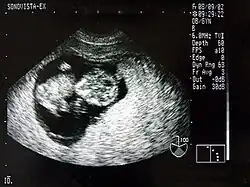

Sonografie einer Schwangeren im Rahmen der Pränataldiagnostik

Ein wesentlicher Vorteil der Sonografie gegenüber dem in der Medizin ebenfalls häufig verwendeten Röntgen liegt in der Unschädlichkeit der eingesetzten Schallwellen. Auch sensible Gewebe wie bei Ungeborenen werden nicht beschädigt, die Untersuchung verläuft schmerzfrei.

Neben der Herztonwehenschreibung (Kardiotokografie) ist sie ein Standardverfahren in der Schwangerschaftsvorsorge. Eine spezielle Untersuchung der Pränataldiagnostik zur Erkennung von Entwicklungsstörungen und körperlichen Besonderheiten ist der Feinultraschall.

2D-Sonogramm eines neun Wochen alten Menschenfötus